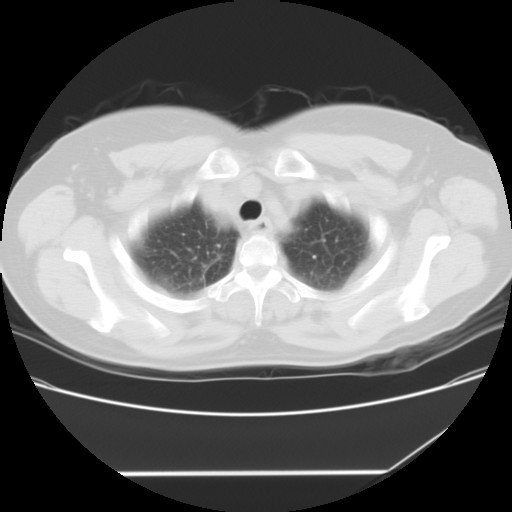

标题: CT24018:女性,62岁,咳嗽4年,无热,胸部CT扫 [打印本页]

女性,62岁,长期咳嗽,既往从事工作有粉尘接触,有高血压病史,110/150mmhg,近日咳嗽加重,脸面浮肿,请大家帮看下,

1、尘肺;2、慢性支气管炎合并肺部感染;3、心影增大(左房、左室大),考虑高血压性心脏病。

慢支并肺部炎症;右肺结核球?主肺动脉、右肺动脉影不宽,右心室不大,不支持肺心病;无心包积液。

间质性肺炎,有纤维化趋势。

1)慢性支气管炎并肺部感染、肺气肿。2)肺间质纤维化。

间质性肺炎,左下肺机化性肺炎。